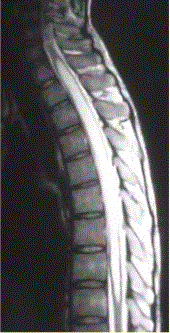

问题 患者女,45岁,胸部不适。影像学检查结果如下图所示。 对病变定位、定性诊断有价值的征象为

选项 A.脊椎增粗 B.邻近蛛网膜下腔变窄 C.病变边界清晰 D.病变特点为一个大囊,其内见一明显强化的结节影 E.病灶内有分隔 F.病灶内可见明显结节样强化

答案 ABCDF

解析 ABCDF